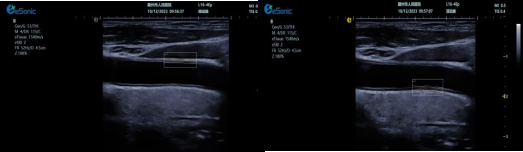

)其他超声技术集成

3377体育超声系统融合 e IMT 内中膜自动测量、超高频高分辨线阵探头、TCCD、心脏彩色多普勒超声等高端台式彩超功能,数据处理能力强,大幅提升人体组织显示分辨率。优势体现为:

? e IMT 内中膜自动测量可自动检测厚度,智能匹配与包络,自动设置取样框,实时或冻结状态下均可测量前壁及后壁厚度,提供多组数值,减少人工误差,便捷准确。

image.png

超高频探头能清晰显示颈动脉内中膜及斑块细节,辅助判断斑块易损性。

? TCCD 技术可评估脑动脉硬化与狭窄程度,全面预警脑卒中风险。

? 心脏彩色多普勒超声有助于判断脑卒中心源性风险因素,完善诊断信息。